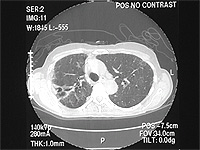

An 80 yr white female presents with four years of dyspnea on exertion, several months of dry cough with one episode of hemoptysis, and unintentional 20 lb weight loss over the past 2 years. She is a nonsmoker. She denied having night sweats, fever, or chills. Her PPD has always been negative, and she worked in an office her entire life. Her physical exam was unremarkable without peripheral adenopathy and clear lungs. Representative chest CT slices are shown:

Bronchoscopy and BAL were performed. BAL showed acid fast positive organisms identified as M. Avium Intracellulare.

Diagnosis

MAI infection. The term "Lady Windermere Syndrome" was first used to describe the infection in elderly women by Reich, et al in 1992. They reported a series of 6 elderly white females with previously healthy lungs who developed MAC lung disease limited to the right middle lobe and lingula. It's unclear what predisposes these patients to infection, but one theory is that voluntary cough suppression in these "prim and proper" ladies leads to poor mucus clearance and increased chance of infection in the already dependent RML and lingula.